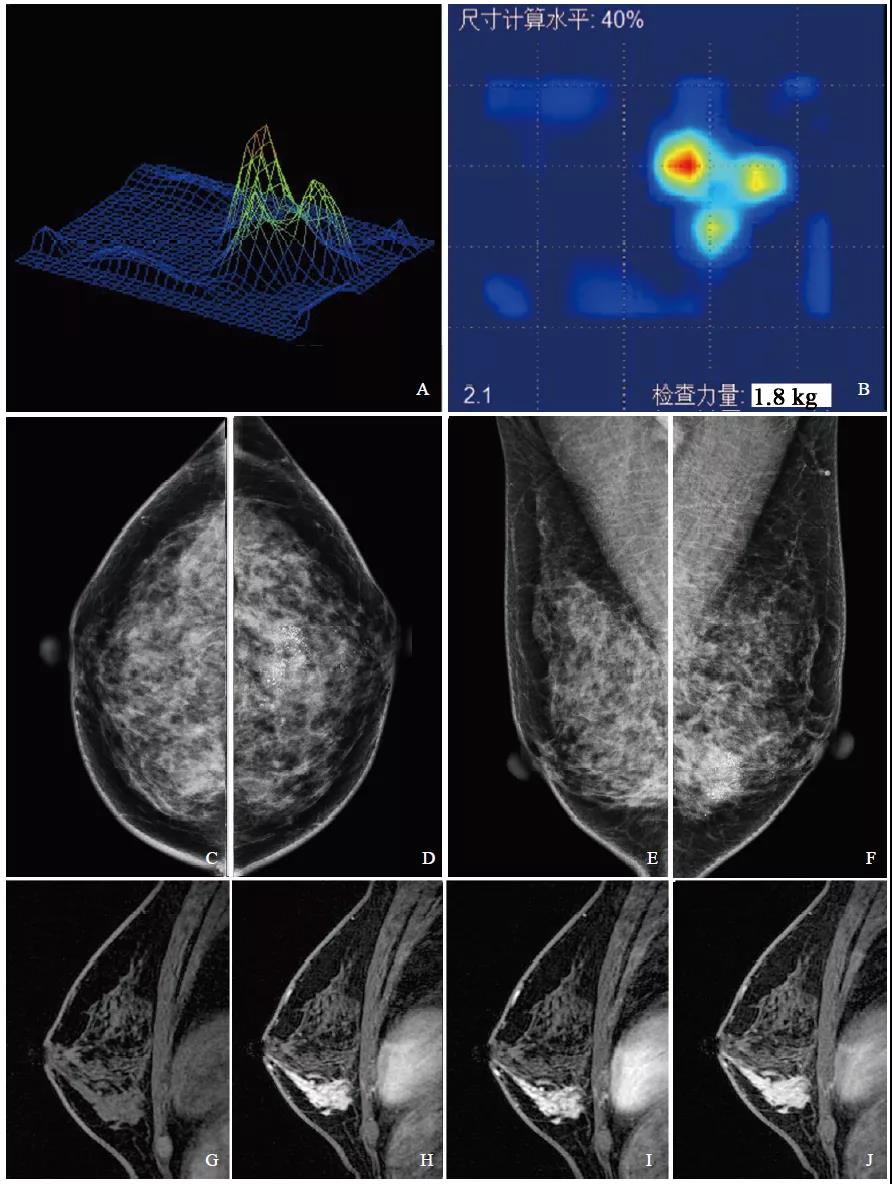

图1 左乳腺浸润性导管癌影像学表现

注:A、B为触诊成像检查3D及2D影像,3D图像呈多峰、峰值高、基底宽、峰顶钝,动态回放肿块活动度差;2D图像中心呈黑色、边界不规则,动态回放内部结构分布不均匀。C~F为乳腺X线摄影图像,乳腺X线纤维腺体类型为致密型。G~J为乳腺MRI动态增强矢状位检查图像,乳腺病变类型为肿块型。